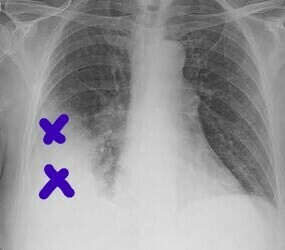

EKG Bulguları: ST segment değişiklikleri troponin sonucunu beklemeden invaziv işlem gerektirebilir.